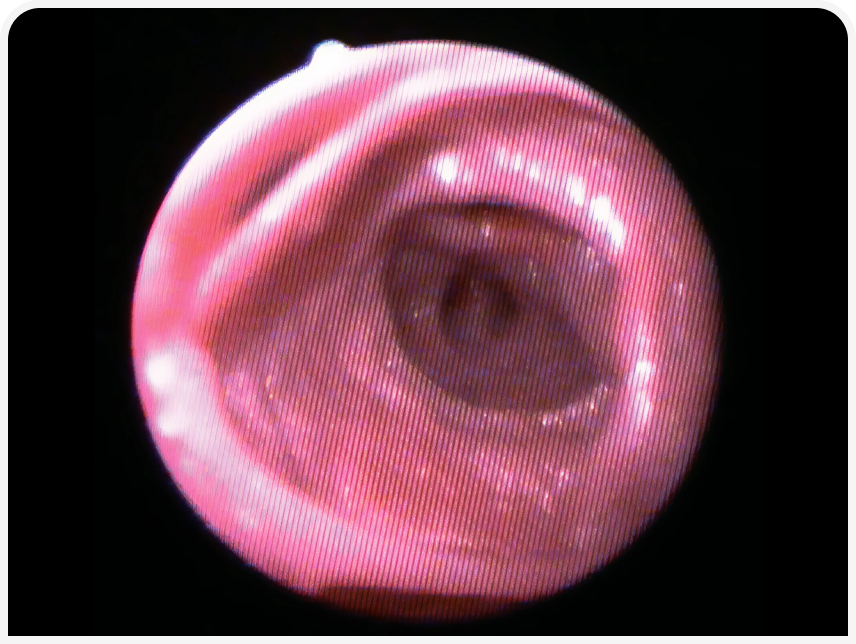

Подтвердить коллапс трахеи и дыхательных путей и оценить тяжесть заболевания можно с помощью бронхоскопии (Рисунок 4). Вероятно, этот метод лучше всего позволяет диагностировать бронхомаляцию сегментов нескольких долей (Рисунок 5), а также подтвердить динамический характер заболевания при поражении небольших сегментов дыхательных путей.

Бронхоскопия также позволяет выявить бронхоэктазы (Рисунок 6) или другие необратимые изменения, такие как бронхитические узелки или воспалительные разрастания в дыхательных путях (Рисунок 7).